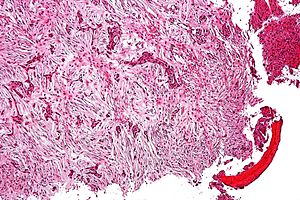

Adamantinoma. H&E stain. | |

| LM | biphasic tumour - epithelial component & fibro-osseous component |

- Biphasic tumour:[2]

- Fibro-osseous component.

- Spindle cells.

- Epithelial component.

- Classically nests of basaloid cells.